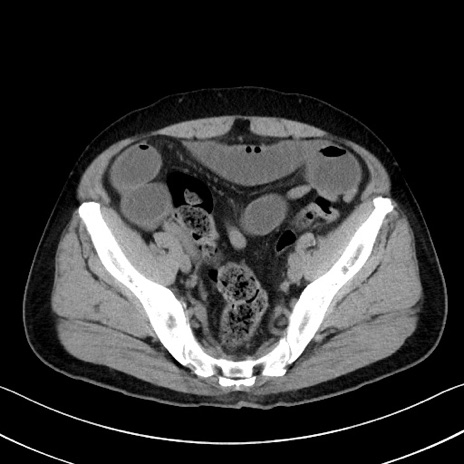

症例35(横断像)

【症例】70歳代 男性

【主訴】腹部膨満、嘔吐

【現病歴】昨日より腹部膨満感出現。本日増悪し、仙痛出現。嘔吐あり、受診。

【既往歴】糖尿病、胆摘後

【身体所見】BP 149/80mmHg、HR 74/min、BT 35.9℃、腹部:膨満、軟、圧痛なし。腸雑音減弱あり。上腹部正中切開瘢痕あり。

【データ】WBC 13500、CRP 1.72